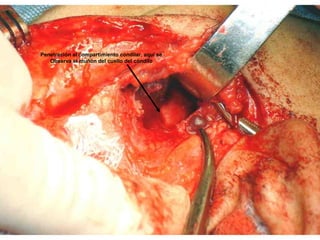

Penetración al compartimiento condilar, aquí se

Observa el muñón del cuello del cóndilo

Condilectomía

Prótesis total de cóndilo, debe cuidarse la relación oclusal.